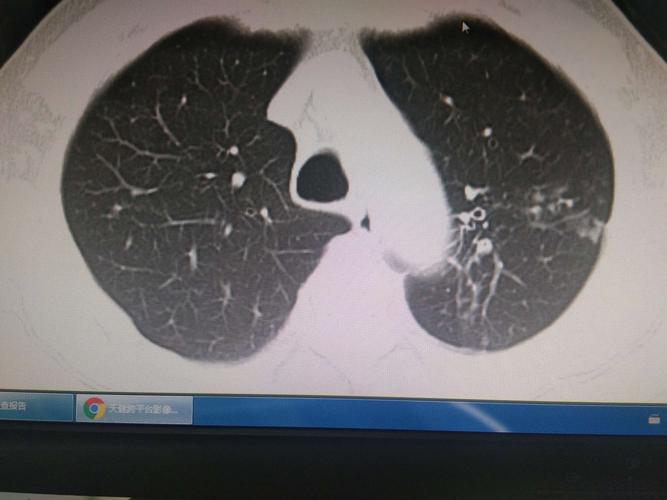

肺结核痰图片大全,肺癌痰图片大全

肺结核图片和正常图片

肺结核图片

肺结核x光片